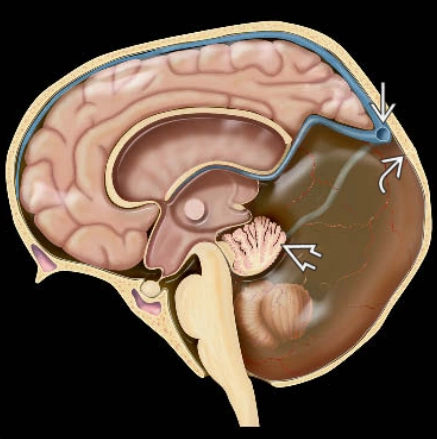

• Bất thường dạng Chiari

• DỊ DẠNG CHIARI TUÝP I (CHIARI I MALFORMATION)

• DỊ DẠNG CHIARI TUÝP II (CHIARI II MALFORMATION)

• DỊ DẠNG CHIARI TYPE III (CHIARI 3)

• Bất thường não sau

• DỊ TẬT DANDY-WALKER (DANDY-WALKER CONTINUUM)